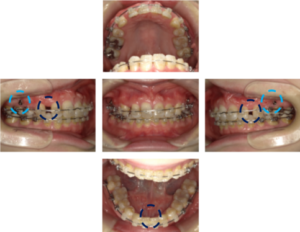

• インサイザー治療中

インサイザー治療中